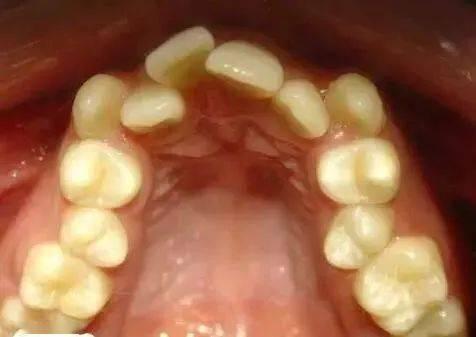

很多時(shí)候,我們總是說(shuō)一個(gè)人的牙齒是女人的第二張臉,尤其是愛(ài)美的女人,當(dāng)牙友們發(fā)現(xiàn)自己有牙齒問(wèn)題的話,都會(huì)想要通過(guò)矯正牙齒來(lái)改善畸形牙齒的情況,因此,很多人紛紛想要整牙。成人牙齒矯正拔牙價(jià)格是多少?一起來(lái)了解一下。

具體的費(fèi)用需要取決于口腔內(nèi)牙齒的具體情況,如果牙齒的畸形程度不嚴(yán)重,僅有2-3顆牙齒是畸形的,這時(shí)矯正起來(lái)比較容易,所需用的費(fèi)用也不會(huì)太多,大概4000元左右就能夠解決問(wèn)題。如果牙齒畸形十分嚴(yán)重,整個(gè)口腔內(nèi)的牙齒都需要矯正,甚至需要拔牙,這樣下來(lái)需要的費(fèi)用可能會(huì)稍微的高一些。如果口腔內(nèi)還有齲齒或者牙髓炎等等疾病,要先將疾病治療,治療之后再進(jìn)行矯正,這樣的費(fèi)用也會(huì)更高。成年人矯正牙齒的費(fèi)用大概從4000-5000元左右到20000-30000萬(wàn)元左右都有可能。

一般在正規(guī)的醫(yī)院進(jìn)行矯正價(jià)格大概在3000-6000元左右,如果到診所一般是2000-4000元左右。齙牙可做前突矯正術(shù),其矯正要排齊且內(nèi)收前牙,改善前突癥狀,因此就需要先拔牙,再做矯正術(shù)。建議你到正規(guī)的醫(yī)院口腔科行前突矯正術(shù)。